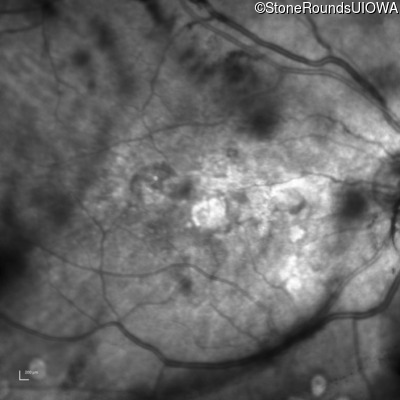

Malattia Leventinese (IIJ)

Malattia Leventinese (IIJ)

This 43 year old woman has experienced a gradual reduction in her central vision for the past 3 years.

| Malattia Leventinese | EFEMP1 | Arg345Trp CGG>TGG | AD |